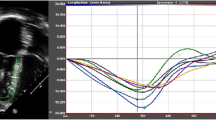

The software, using reflected speckles, automatically traces the boundaries of the RV in the longitudinal 4-chamber view at end diastole and end systole and in three corresponding short-axis cuts at preset levels of the RV. Following automated tracing of the endocardium by the system, additional manual adjustments are feasible. Whenever, the final adjustments are approved by the operator, the RV endocardial surface is automatically traced over the entire cardiac cycle and values of RV diastolic, systolic, and stroke volumes in addition to EF are provided (Fig. 2). The change in RV volumes over time is depicted as a dynamic 3D cast (Fig. 3).

RV endocardial surface is automatically traced over the entire cardiac cycle and is depicted in 3 short and one 4-chamber cuts, both in diastole and systole. Values of RV diastolic, systolic, and stroke volumes and EF are provided. Adjustments in every image and frame are feasible. EDV end-diastolic volume, EF ejection fraction, ESV end-systolic volume, Ch chamber, RV right ventricle, SAX short axis, SV stroke volume

In addition to volumetric data, 2D measurements including tricuspid valve annulus (TVA) diameter, TAPSE, FAC, and free wall LS could be extracted from a non-shortened 4-chamber image derived from the same 3D dataset. Using STE, TAPSE was calculated as the difference in the distance between RV apex and the lateral aspect of the annulus at end diastole and systole. When measuring FAC, the trabeculations were included in the cavity of the RV in diastole. The free wall LS is an automated measurement as well. It was calculated as the difference in length of the line tracing the endocardial surface of the RV free wall from the apex to the lateral TV annulus in diastole (L0) and systole (L1) as per the following formula: LS = (L0 − L1/L0) * 100 (Fig. 4).

Non-foreshortened 2D images of the RV at end diastole and end systole. The free wall LS was calculated as the difference in length of the line tracing the endocardial surface of the RV free wall from the apex to the lateral TV annulus in diastole. LS longitudinal strain, RV right ventricle, TV tricuspid valve